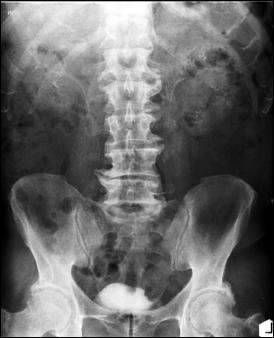

Diagnosticul diferential cu tuberculoza urogenitala

Vezica urinara are contururi greu delimitabile pe cistografie si pacientul are ureterohidronefroza bilaterala.

|

Figura 57. Vezica urinara mica |

Vezica urinara mica, scleroasa, cu rinichi drept unic chirurgical, uretero-hidronefroza gr I

Figura 59. Vezica urinara "crispata", cu ureterohidronefroza bilaterala. |